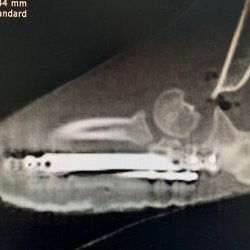

Rozárka je fenečka dovezená ze Slovenska, z romských osad. Po příjezdu do spolku Pro psí duši, z.s. kulhala na levou přední nohu, bez jakéhokoli zlepšení. Zjistilo se, že má vrozenou vadu. V lokti neměla dorostlou kost ke kloubu a nemohla se proto plně na nohu opírat. Rozárka tedy musela absolvovat náročnou a velice nákladnou operaci, bez které by nemohla nožku po celý život běžně používat.

Zjistilo se také, že tato úžasná fenečka měla rozdrcený kloub, při růstu jí jedna kost zůstala nespojena s kloubem a druhá byla moc dlouhá. Prodělala tedy nakonec operace rovnou dvě. Ačkoli se Rozárka narodila do prostředí, kde nepoznala, co je člověčí láska, nýbrž špatné zacházení, nakonec se na ní štěstí usmálo. Zamilovala se do ní jedna veterinární sestřička z Prahy. Rozárku už má u sebe doma, kde spolu rehabilitují a aplikují vodní lázně.

Průběh operace

RTG snímek končetina Rozárka